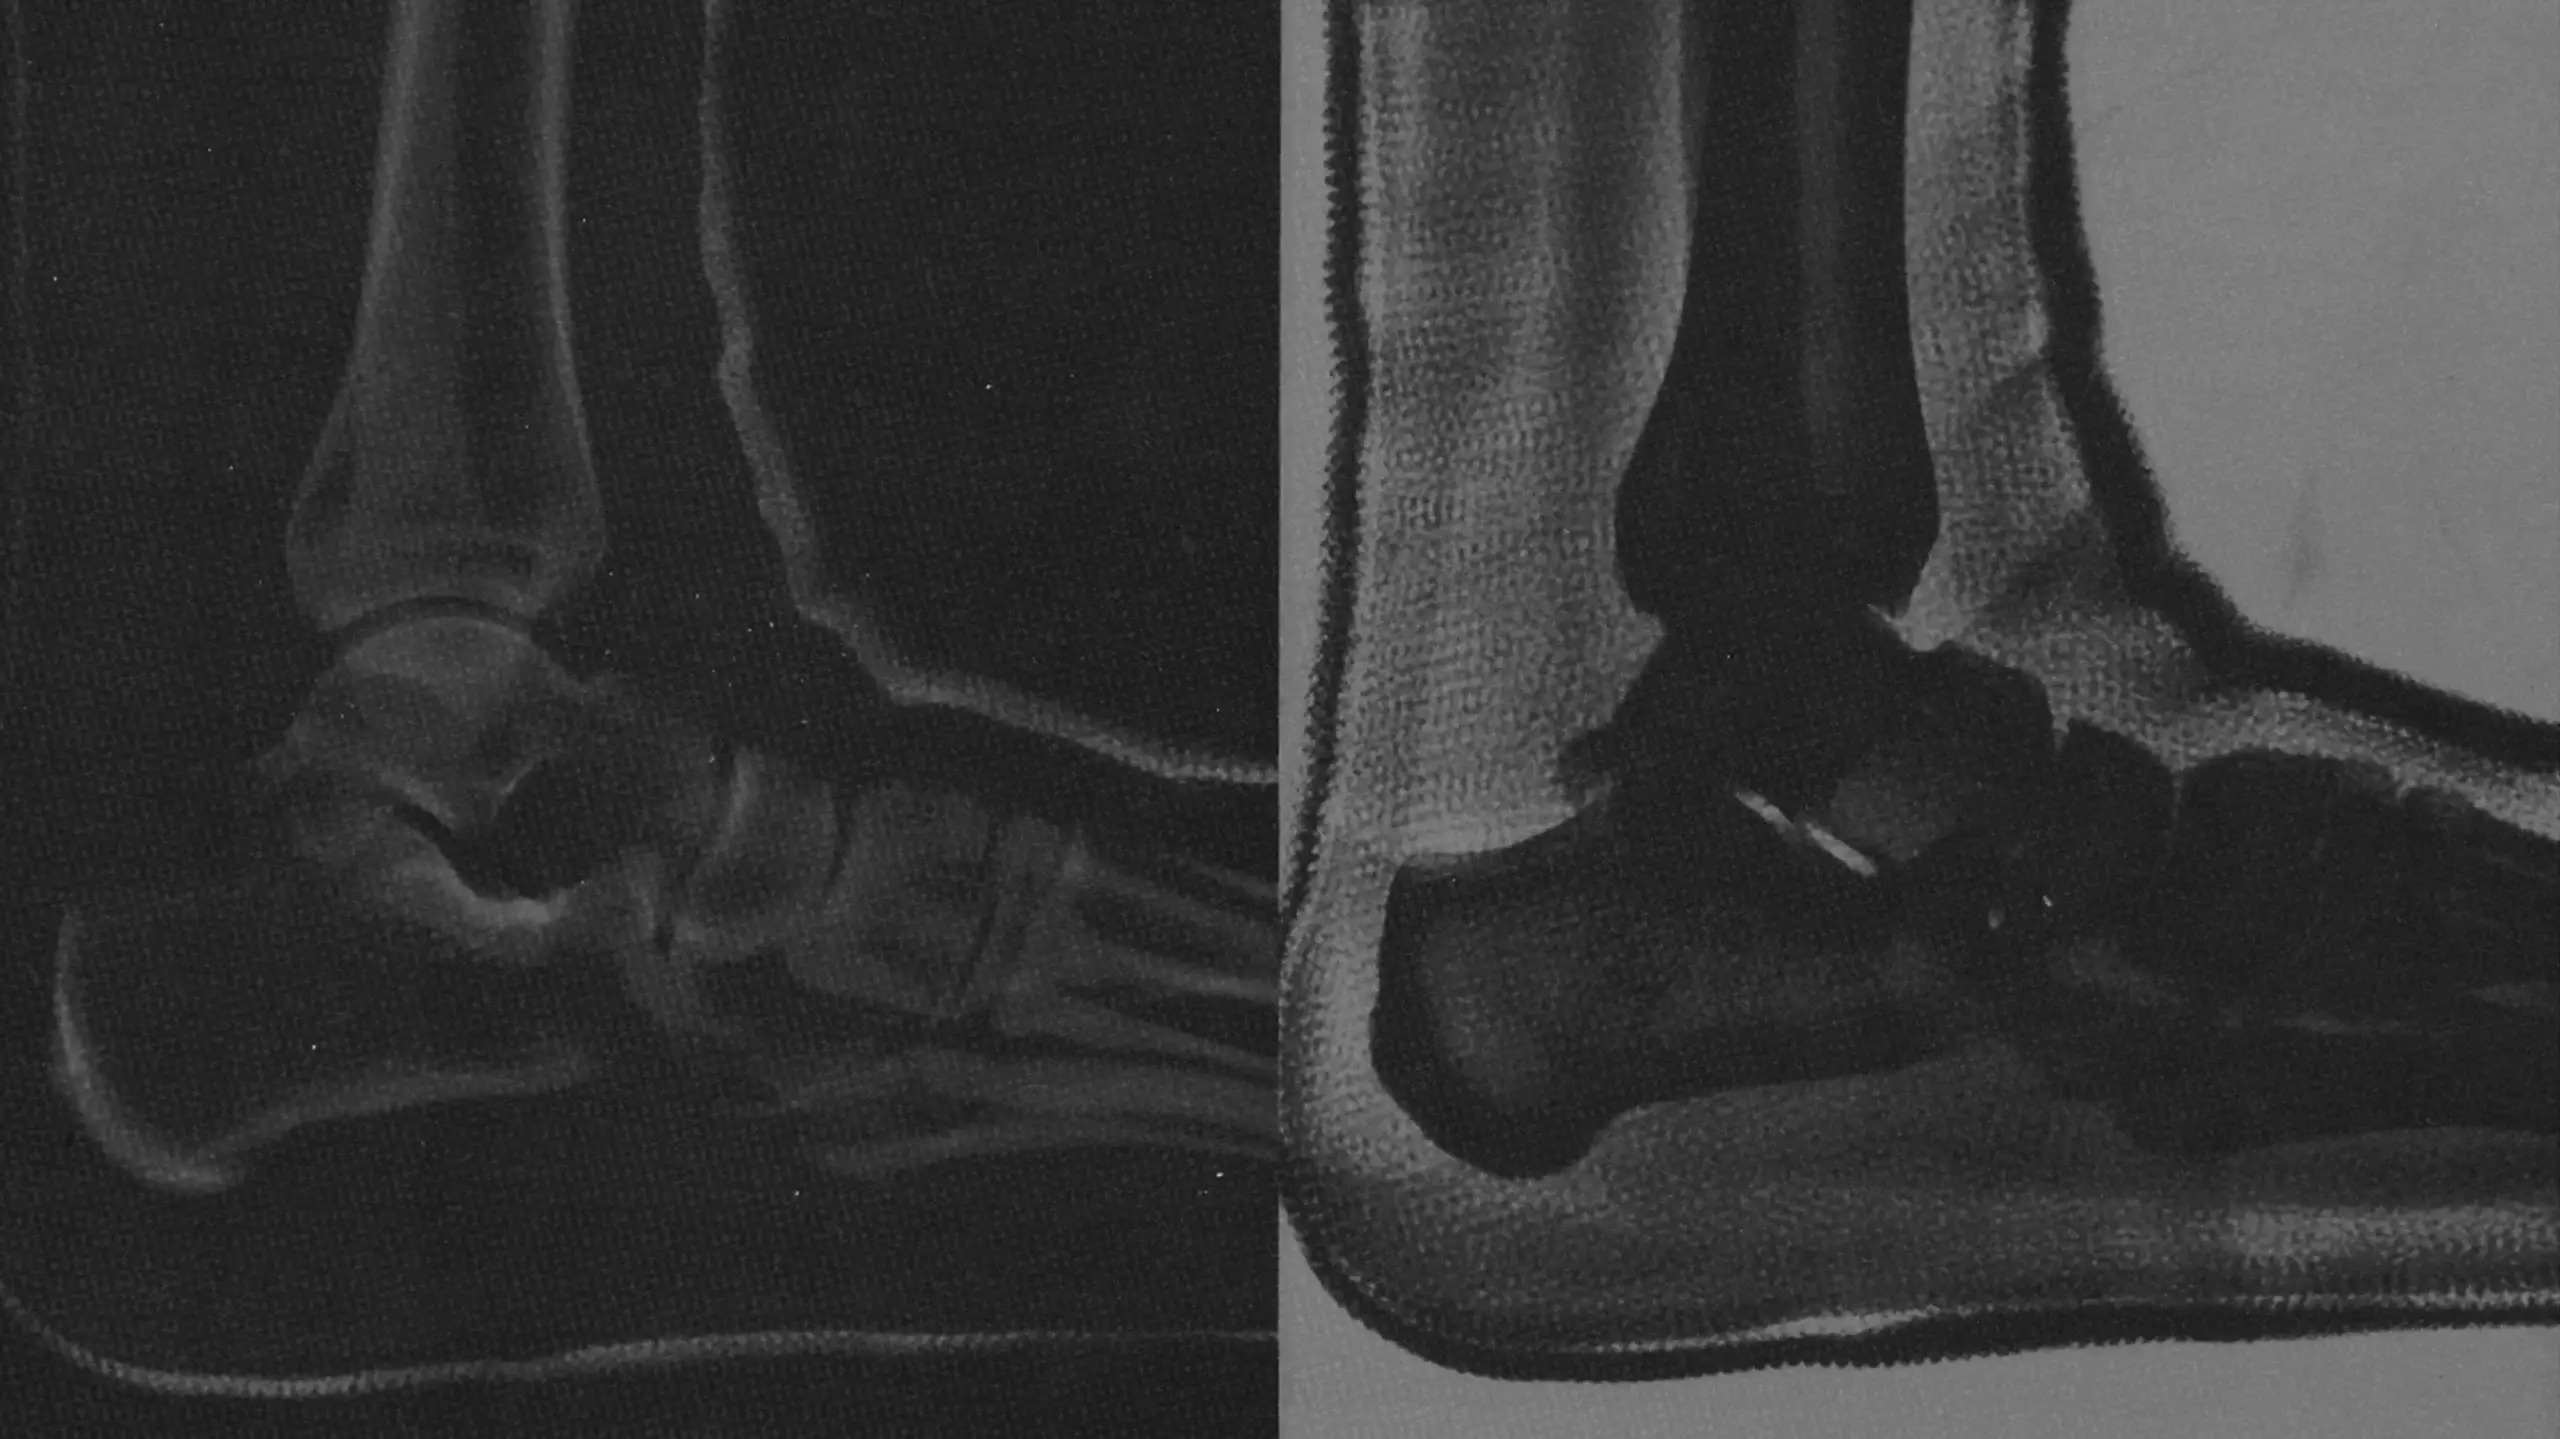

While returning from a trip, I fell from a moving train and badly injured my ankle.

I was unable to walk. Later, medical reports confirmed an ankle fracture, and a cast was placed around my left foot, restricting my movement for a few months.